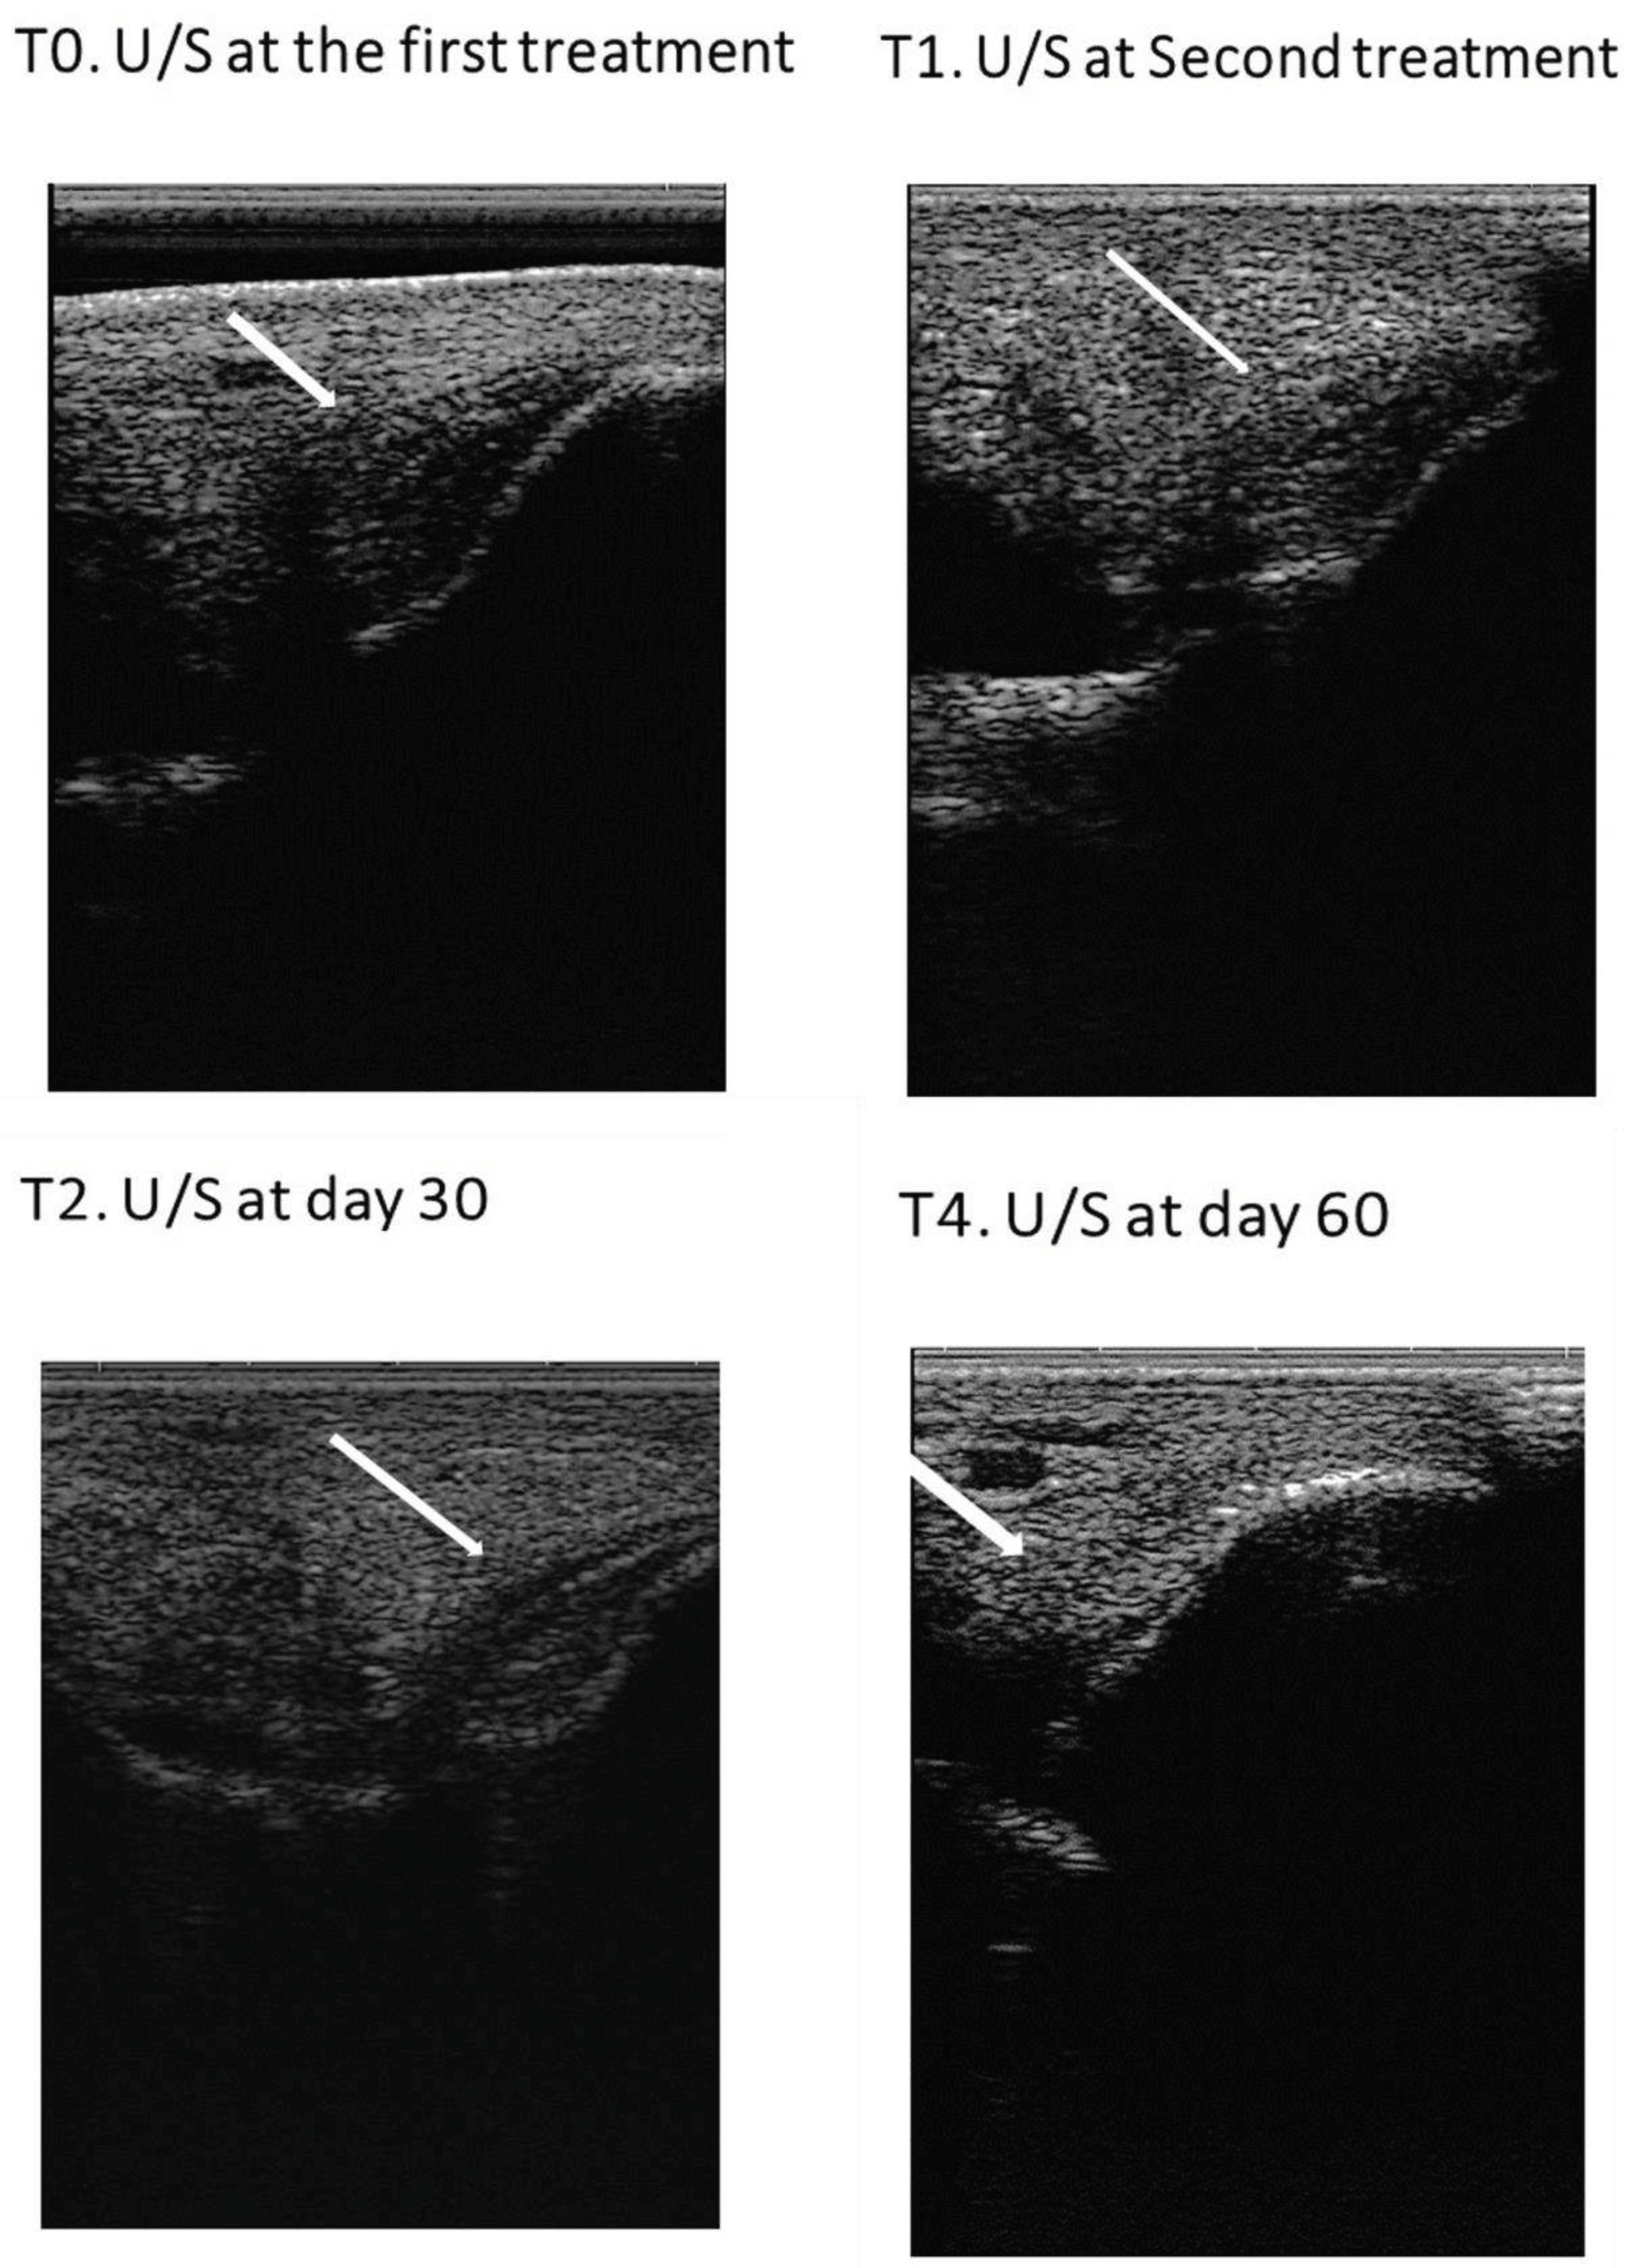

Tissue regeneration was indirectly estimated through lameness evaluation, pain to pressure, limb inflammation, limb sensitivity and ultrasound image. In each assessment, the ultrasonographic exam was performed in transverse and longitudinal scans and three parameters were evaluated: lesion echogenicity, lesion longitudinal fiber alignment (FA) and cross-sectional area. The contralateral healthy limb was used as a control. Ultrasonographic evaluation was performed on assessment day, treatment day (day 1 – T0) and on days 15 (T1 – second administration), 30 (T2), 45 (T3), 60 (T4) and 90 (T5) post-treatment (Figure 4).

At day 30 (T2), increased echogenicity of the lesion was evidenced as well as reduction of cross-sectional area with good fiber alignment. There was also no evidence of pain and lameness. Fluid within the joint reduced as well as joint swelling. Nevertheless, compared with the contralateral limb, the right tarsocrural joint diameter was larger than the left.

Over the course of the follow-up ultrasonographic examinations, an increasing echogenicity of the lesion was evidenced, as well as a reduction of the cross-sectional area, good fiber alignment and reduction of the abnormal synovial fluid. At day 60 (T4), two months after the first treatment, there was a complete recuperation of the ligament structure – lesion completely fulfilled, good echogenicity, good fiber alignment and normal cross-sectional area – compatible with adequate tissue regeneration. No pain and no lameness were present, as well as no signs of cartilage remodeling. Despite this achievement, physical rehabilitation program was followed as stated until day 90 (T5).

Lesion ultrasonographic improvement and indicators of regeneration were evidenced by progressive increase in echogenicity and fiber alignment, and decrease of ligament cross-sectional area and synovial fluid accumulation within the joint space, appreciated through ultrasound examination during the follow-up at day 1 (T0), 15 (T1), 30 (T2), 45 (T3) and 60 (T4) (Figure 11).

Figure 11. Images of ultrasonographic follow-up. (a) Day 1 (T0), (b) day 15 (T1), (c) day 30 (T2) and (d) day 60 (T3). Indicators of ligamentar regeneration: increased echogenicity and fiber alignment, decrease of cross-sectional area and synovial fluid accumulation within the joint space.